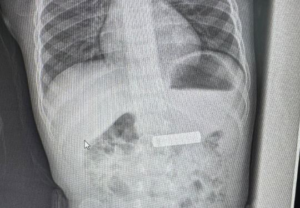

Elezi ka postuar edhe fotografi se si dukje bateria në stomakun e fëmijës, dhe pas nxjerrjes së saj.